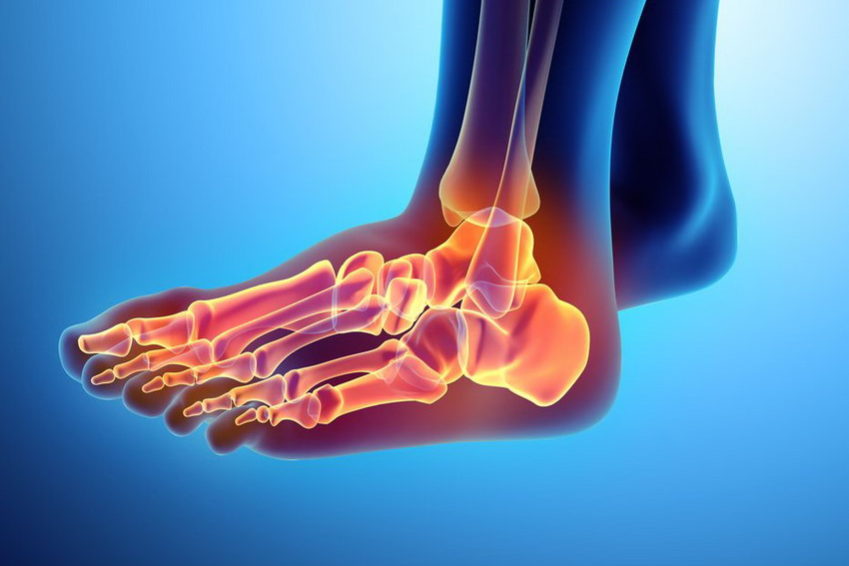

Peace & Love, czyli o niebanalności skręcenia stawu skokowego! Skręcenie stawu skokowego to jedna z najczęstszych kontuzji sportowych, „sprawiedliwie” dotykająca różnych dyscyplin. Popularne „ skręcenie kostki” to prawie 25% wszystkich urazów narządu ruchu zgłaszanych na oddziałach ratunkowych i stanowiące 50% wśród urazów sportowych (1). Aż 70% osób pośród nas doznało co najmniej raz w życiu…